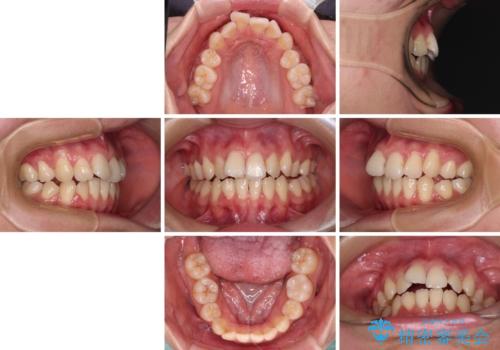

- 抜歯矯正の後戻りを気にして来院された患者様です。

舌の突出癖によるオープンバイトになっていたため、インビザラインによるマウスピース矯正をおすすめしましたが、自己管理の自信がないとのことで、ワイヤー装置による矯正治療を行うこととしました。

舌の突出癖が認められると、上下前歯の隙間を閉じることができません。

舌のトレーニングをしっかりと行っていただくことで、歯列を整えることができます。